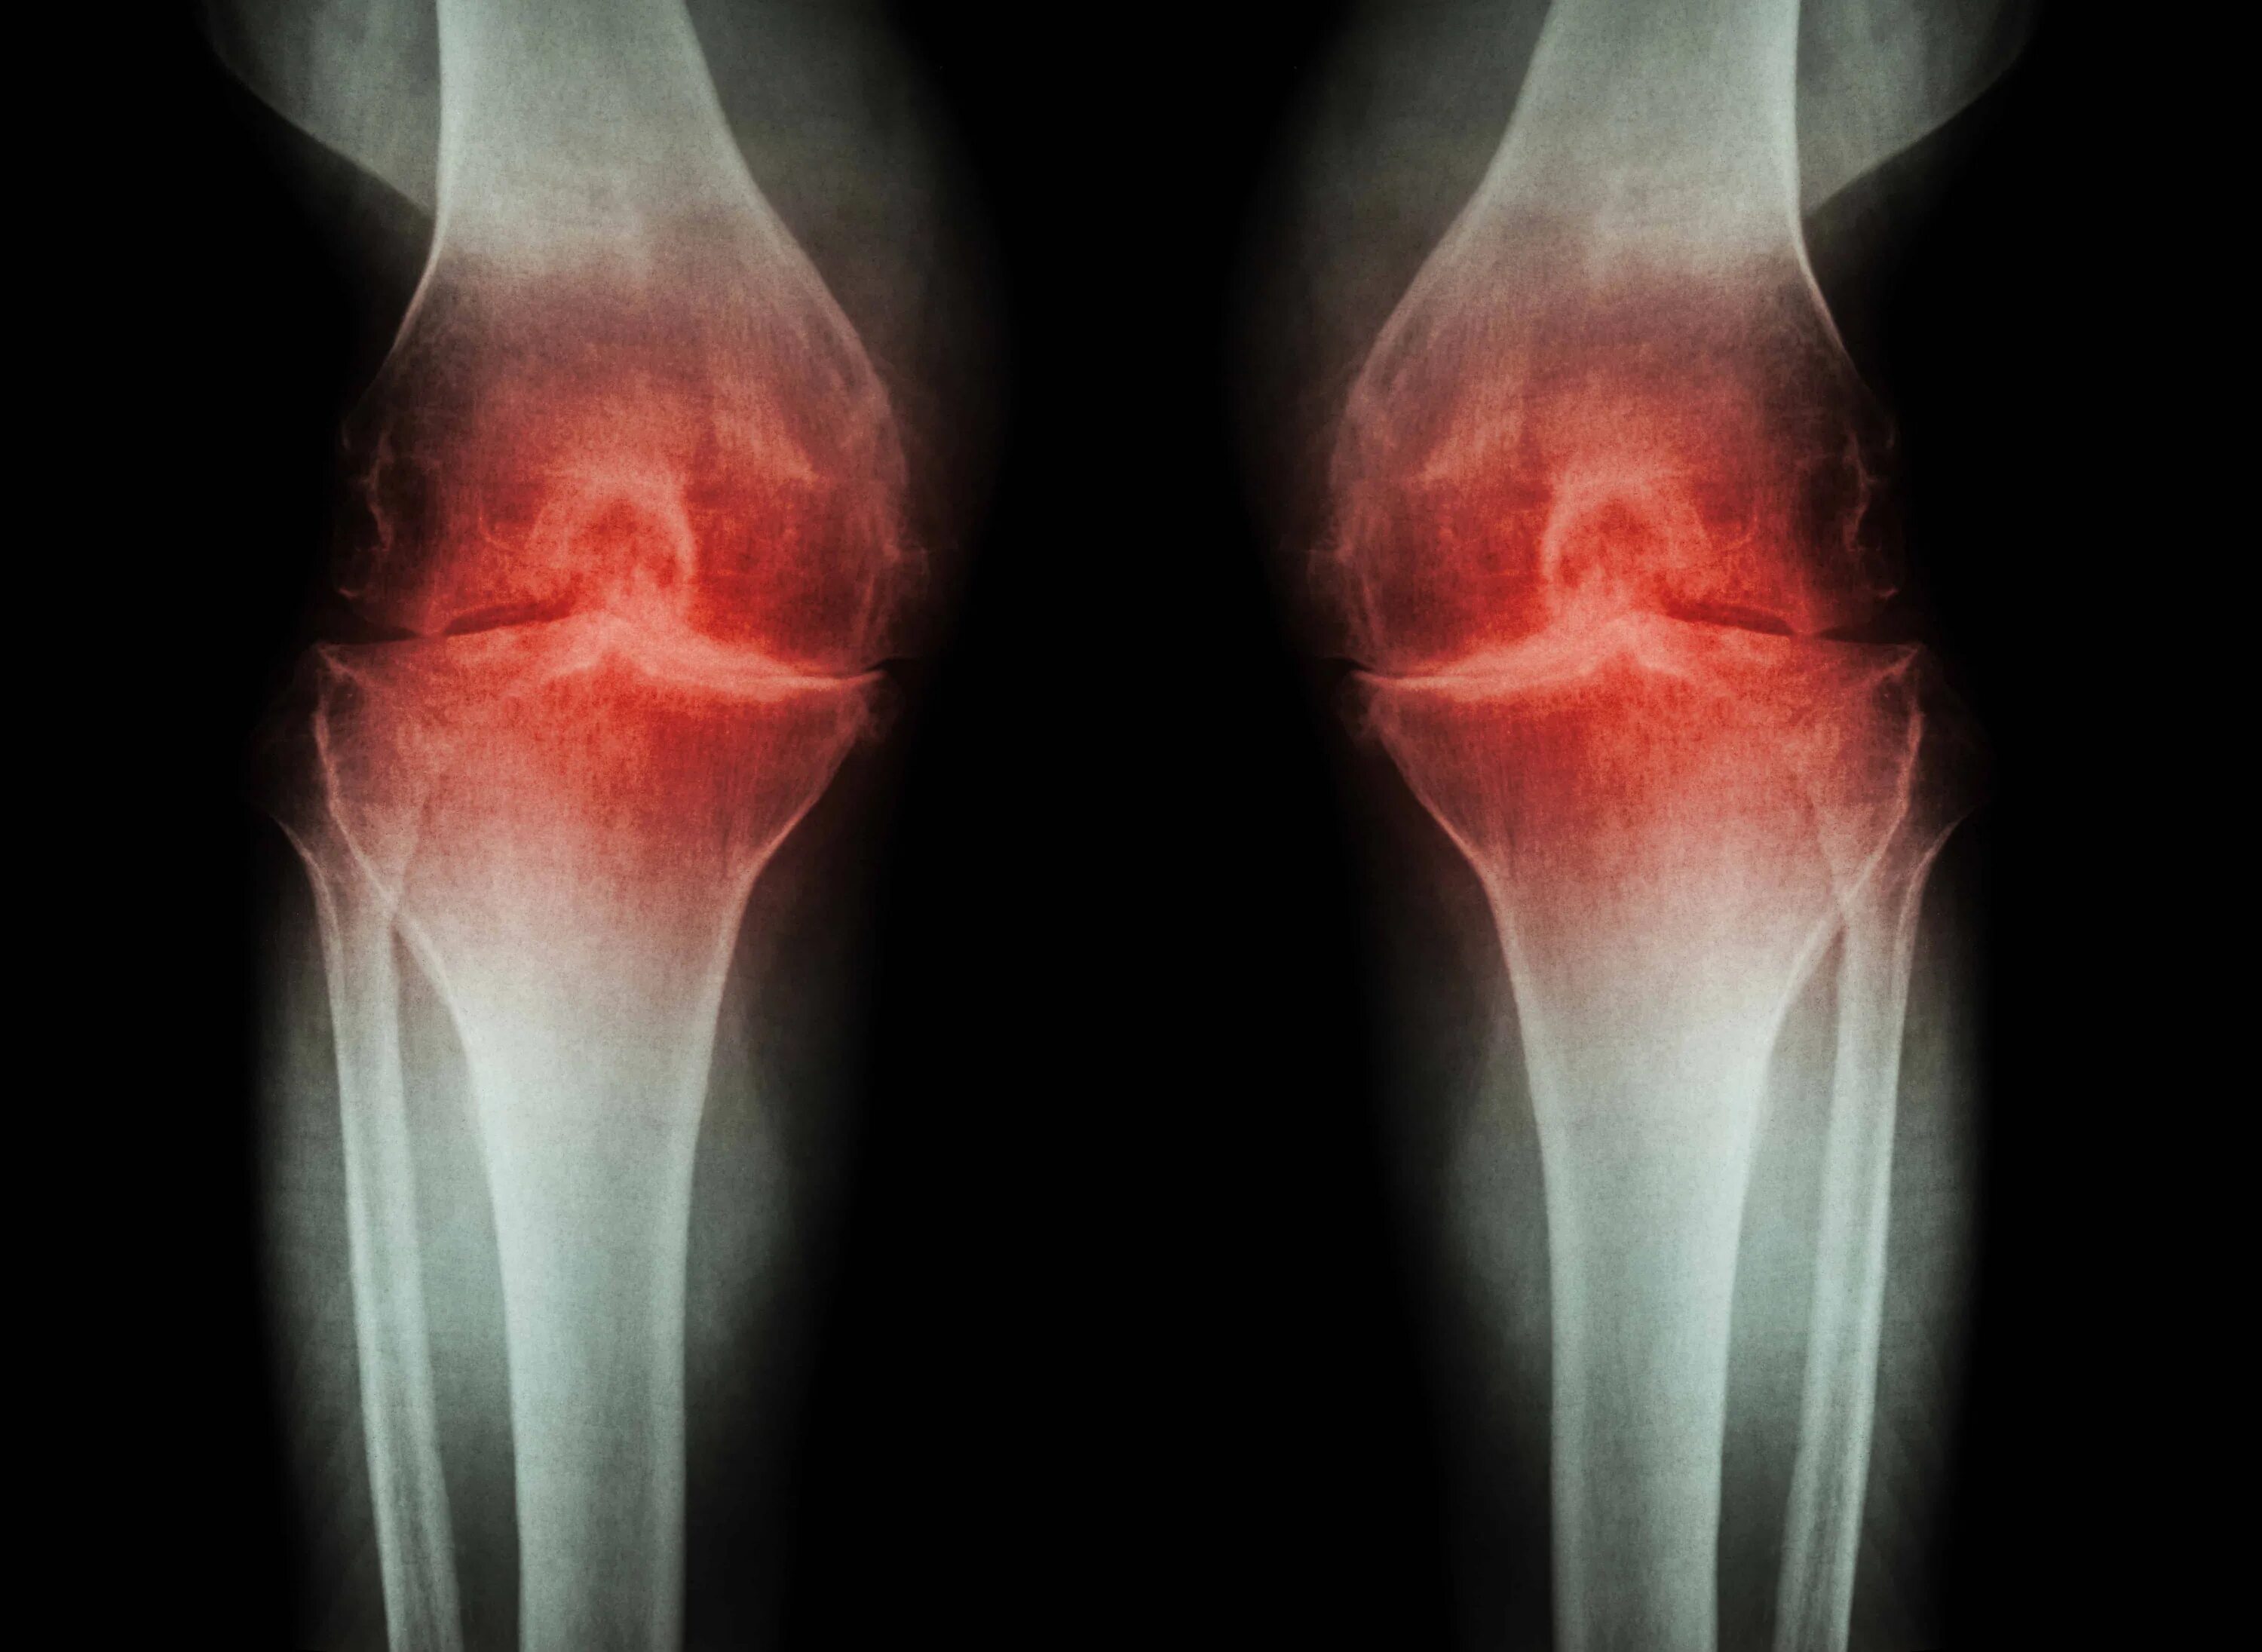

Артроз колен видео